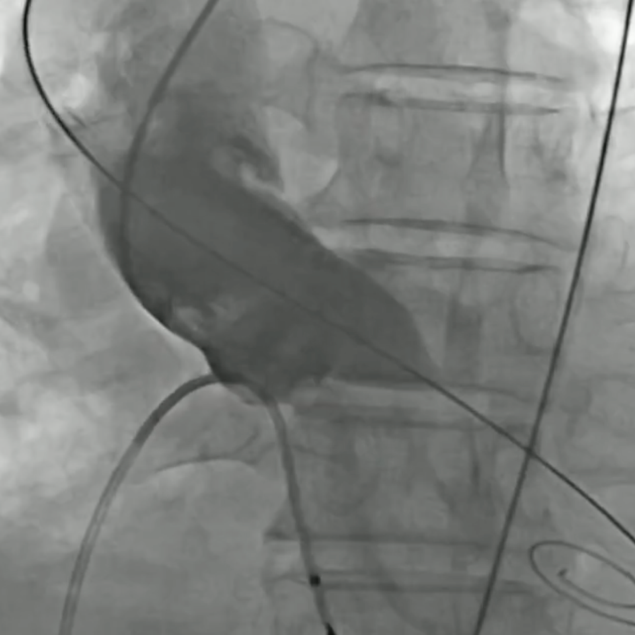

小球囊预扩张

20mm球囊预扩张

双平面造影确认植入位置

释放完成